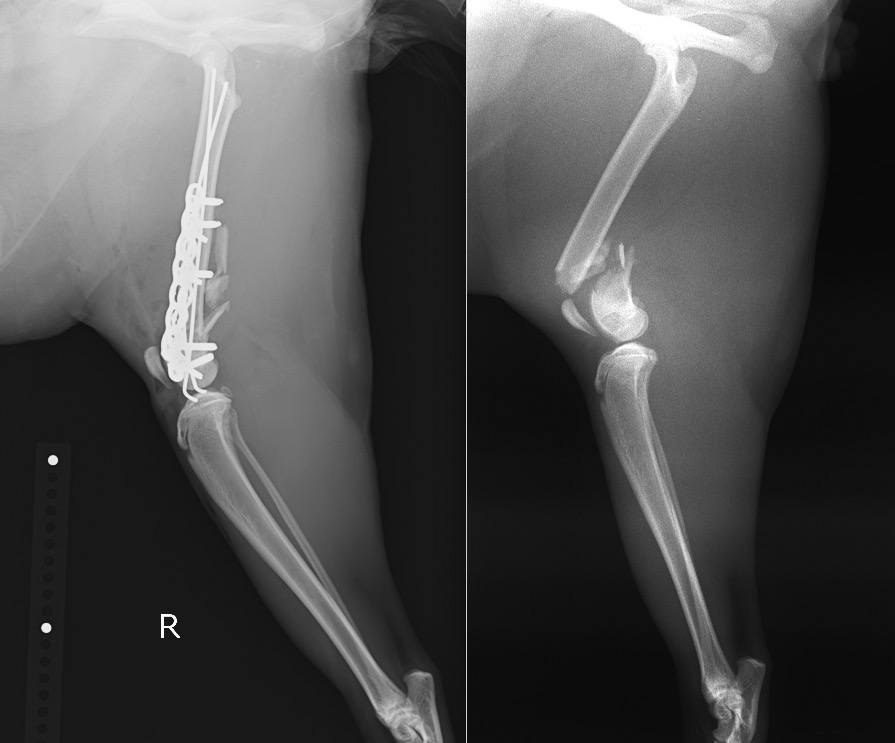

外科療法は内外側から2本のピン(髄内ピン、ラッシュピン)を挿入し、外側に2.4㎜ロッキングプレート(LCP)、内側に2.0mmロッキングプレート(LCP)を設置、強固な固定を目指しました。

右後肢側面像 術後/術前

右後肢正面像 術後/術前

術後の経過は良好であり、退院する頃には手術をした右の後ろ足も使って自分で歩いてくれるようになっています。